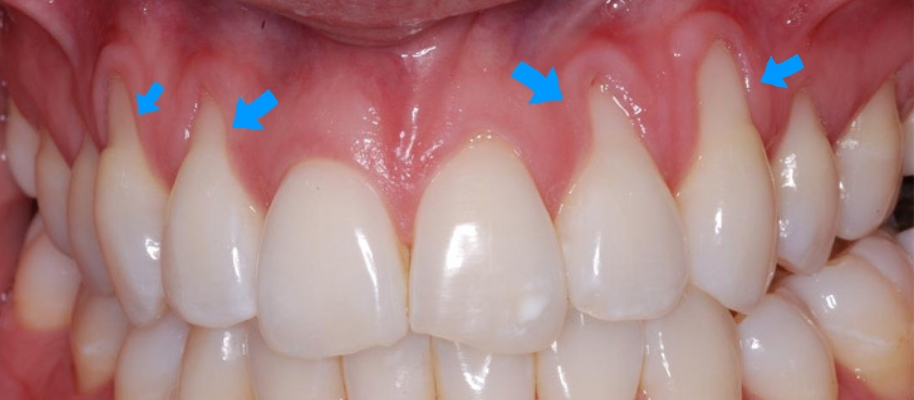

La recessione gengivale è un processo che si manifesta gradualmente nel tempo e non improvvisamente. I sintomi sono rappresentati da un progressivo ingiallimento dei denti, che risultano particolarmente sensibili ai cibi freddi, agli acidi ed agli zuccheri. L’ipersensibilità dentinalepotrebbe provocare anche maggiori disturbi al dente del giudizio ed agli altri denti in generale, spingendoti a spazzolare meno intensamente per alleviare il fastidio. Si innesta così un circolo vizioso che favorisce la formazione e la proliferazione dei batteri nel tuo cavo orale, causa principale della formazione di placca e tartaro che possono portare alle carie. La retrazione gengivale può provocare problemi anche molto fastidiosi come l’alitosi o le gengive sanguinanti, gonfie ed arrossate. Aumentano anche le difficoltà masticatorie e nei casi più gravi c’è il rischio di perdere il dente.Anche da un punto di vista estetico si palesano inestetismi piuttosto antipatici. I denti appaiono più lunghi, mentre le radici dentali sono più visibili ed esposte. Il colore dei denti tende ad ingiallirsi, una situazione imbarazzante che può rendere il tuo sorriso meno smagliante. Negli stadi più avanzati la recessione gengivale può provocare lo spostamento e addirittura la perdita dei denti.